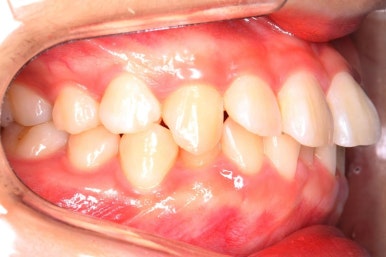

위 사진은 연산동교정치과 처음 내원하셨을 때의 입안 모습입니다. 몇 가지 모습이 관찰됩니다.

치아가 삐뚤삐뚤합니다.

위~아래 앞니가 많이 겹쳐서 아랫니가 많이 모이지 않는 "과개교합" 입니다.

앞니가 앞으로 뻐뜨러져 있습니다.